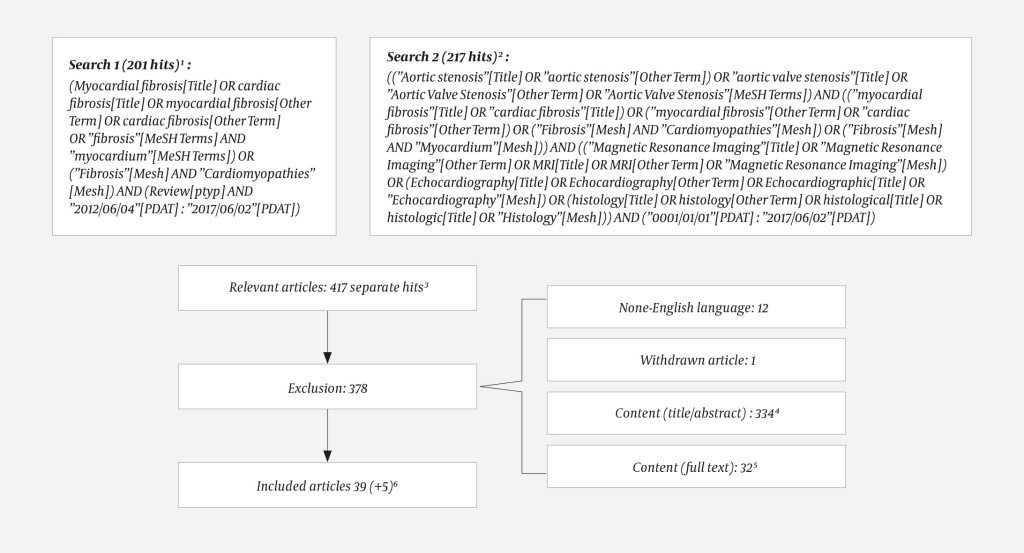

The article is based on two complementary literature searches conducted in PubMed on 2 June 2017. First, we searched for review articles from the last five years in which the terms "myocardial fibrosis" or "cardiac fibrosis" were used in the title, or occurred as MeSH terms (medical subject headings) or as other terms (author's tagging of article). In the second search, we combined searches for "aortic stenosis" "myocardial fibrosis" with detection methods (cardiac MRI, echocardiography or histology, with synonyms). Without defining time limits, we searched for the terms in the title, MeSH or other terms. The search details with number of hits, excluded and included articles, are illustrated in Figure 1. The first author excluded 378 of 417 hits on the basis of content. Five articles were added. A total of 44 articles were included, and all were read in full text.